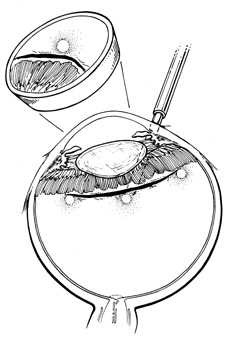

Current cryotherapy instrumentation employs expansion of high-pressure nitrous oxide at the tip of a probe generating temperatures as low as 89°C. The temperature effect is confined to the tip of the probe by an insulating sleeve. A probe 2.0 to 2.5 mm in diameter usually is used for retinal work. Treatment of retinal breaks and pathologic conditions requires accurate placement of the cryoprobe tip. The surgeon must be certain that the indentation visualized with the indirect ophthalmoscope is the tip of the probe and not the shaft. Confusion between the tip and the shaft of the cryo-probe can cause inadvertent posterior freezes.33 To minimize the possibility of this complication, the surgeon must indent only with the tip of the cryoprobe (Fig. 10). It is also helpful to perform the first freezes at the most anterior aspect of the area requiring treatment to assess both location and intensity of treatment.

Fig. 10. A. Inadvertent posterior placement of cryoprobe tip caused by visualization of cryoprobe shaft. B. Correct placement of cryoprobe tip.